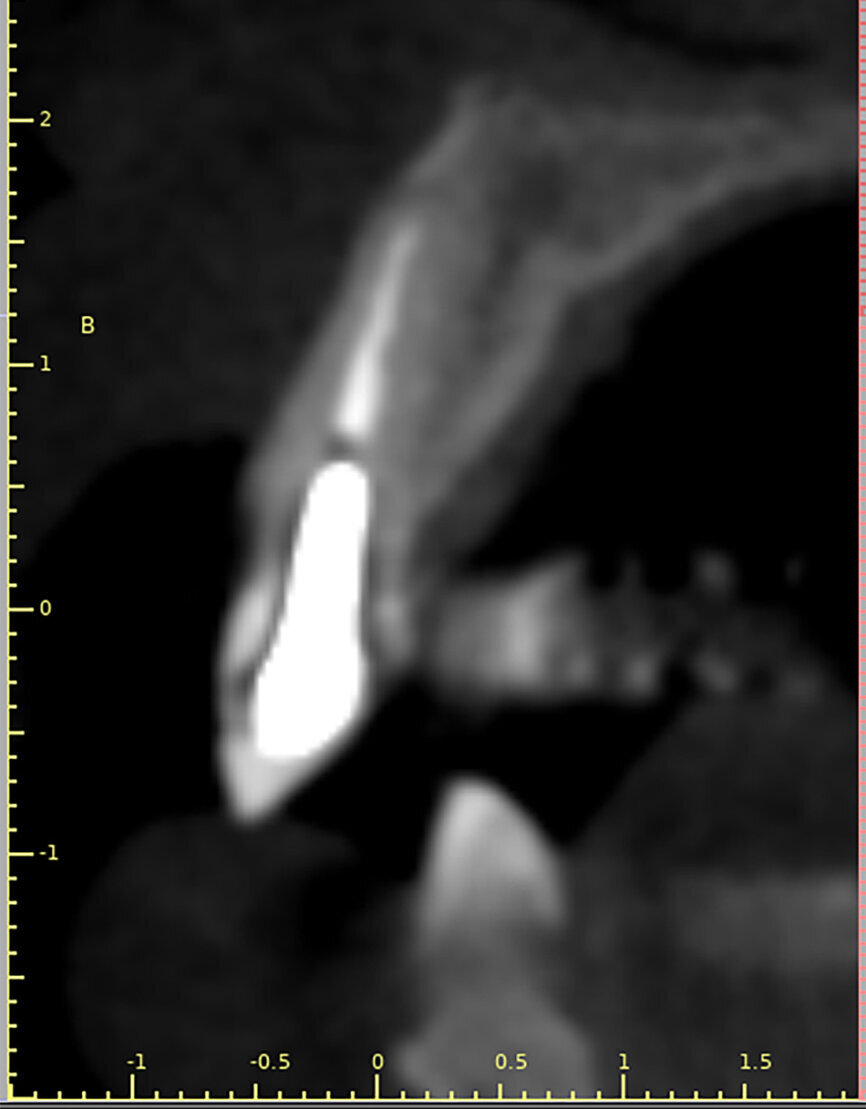

Fig. 14a:

The CBCT cross-sectional image revealed a favourable pre-op condition for a PET procedure.

Fig. 14b: Using the native Carestream 3D Imaging Software,

a simulated implant (red outline) and abutment projection (yellow outline) was positioned within the available bone to avoid the root fragment.

A 62-year-old male patient presented with a hopeless prognosis for a post fracture in the left central incisor requiring extraction (Figs. 12a & b). The preoperative periapical radiograph revealed an existing implant supporting a metal–ceramic restoration for the adjacent region #11 (Fig. 13). The CBCT (CS 9600, Carestream Dental) cross-sectional image revealed a favourable preoperative condition relating to the trajectory of the endodontically treated root to the alveolus for a PET procedure (Fig. 14a). Using the native Carestream 3D Imaging software, a simulated implant and abutment projection was positioned within the available bone to avoid the root fragment (Fig. 14b).